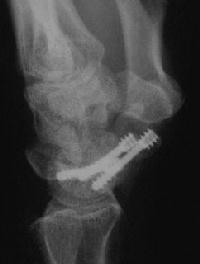

Case 8. Transscaphoid perilunate fracture dislocation...

Click for larger image

Two screws put in dorsally, LT ligament reinforced with a strip of extensor retinaculum left attached to the triquetrium and anchored into the lunate; temporary capitolunate pin.